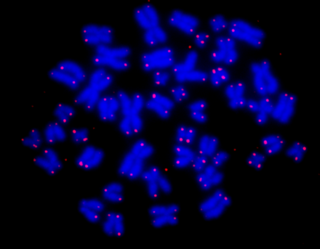

我们先来了解下什么是端粒。端粒是一小段DNA-蛋白质复合体,存在于染色体末端,用于保护DNA主要部分不在细胞分裂期间受损,端粒的长度反映细胞复制史及复制潜能,随着年龄的增长,端粒长度往往会缩短。端粒越短,表明细胞的寿命越短;越长,表明细胞的再生能力越强。所以,端粒的长短意味着衰老的程度。

端粒位于染色体末端(图片来源:NASA官网)